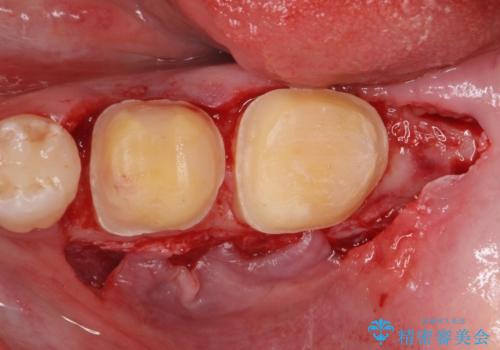

APF(歯肉弁根尖側移動術)

銀歯を外して被せ物の予定でしたが歯の高さが低く取れやすい被せ物になってしまうため歯の高さを変える手術を行いました。

まずはメタルを全て外し仮歯にして、手前のメタルインレーは手術前にセラミックインレーの治療を行いました。